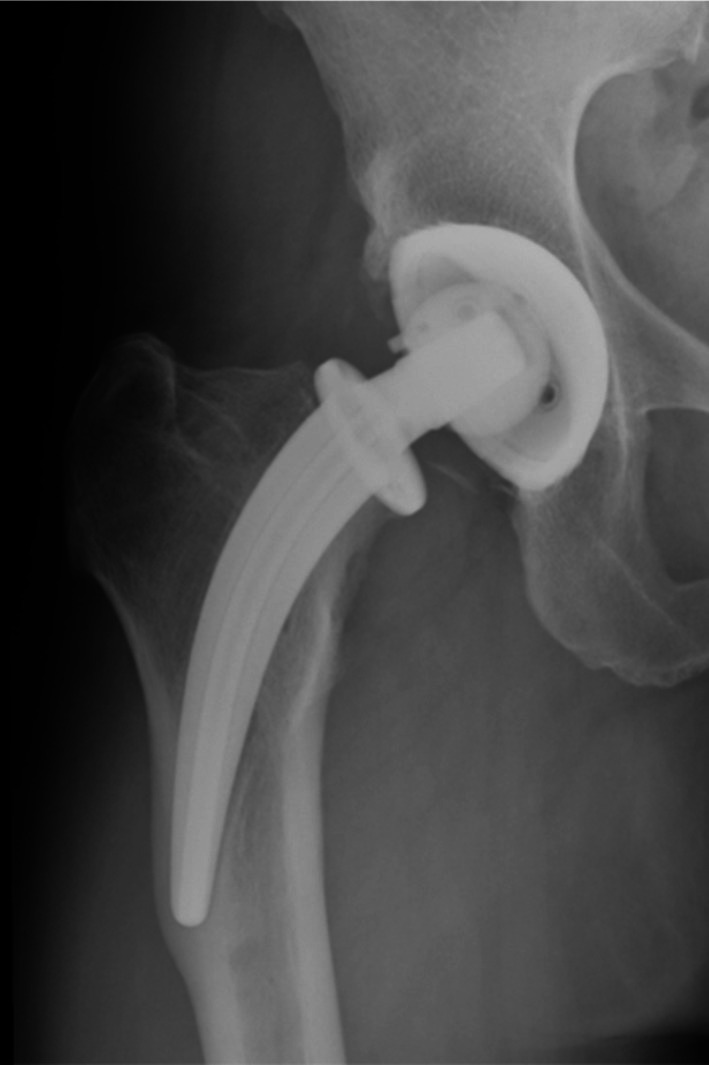

Objective: The Collum Femoris Preserving (CFP) stem offers biomechanical advantages in total hip arthroplasty (THA). However, aseptic loosening remains the most common cause of failure and other severe complications, with specific risk factors associated with the CFP stem remaining inadequately defined. This study aims to investigate the possible factors associated with aseptic loosening.

Methods: This study retrospectively analyzed patients who underwent primary THA with the CFP stem from January 2004 to December 2009 in our institution. Patients were divided into two groups based on whether there was aseptic loosening. Demographic and imaging parameters were collected from medical records and the hospital's Picture Archiving and Communication System (PACS). Comparative analyses were conducted, and variables with significant differences were subjected to Cox regression to identify independent risk factors of aseptic loosening.

Results: A total of 469 hips were included, with 52 hips (11.1%) of aseptic loosening identified. Seven independent risk (protective) factors were found, including ceramic-on-polyethylene (COP) bearing surfaces (Hazard Ratio = 2.084, 95% Confidence Interval: 1.043-4.166, p = 0.038), history of steroid therapy (HR = 2.393, 95% CI: 1.056-5.425, p = 0.037), neck resorption ratio (NRR) (HR = 1.019, 95% CI: 1.005-1.033, p = 0.008), bone mineral density (BMD) (HR = 0.933, 95% CI: 0.891-0.976, p = 0.003), canal fill ratio (CFR) (HR = 0.951, 95% CI: 0.923-0.980, p = 0.001), cortical index (HR = 0.933, 95% CI: 0.891-0.976, p = 0.003), and varus/valgus angle between 3° and 6° (HR = 4.427, 95% CI: 2.303-8.509, p < 0.001), varus/valgus angles > 6° (HR = 8.854, 95% CI: 3.704-21.165, p < 0.001).

Conclusion: This study identifies key risk factors contributing to aseptic loosening, including COP bearing surfaces, steroid therapy history, excessive femoral neck resorption, and significant varus/valgus malalignment. Conversely, higher BMD, improved cortical index, and favorable CFR were protective against loosening. These findings underscore the need for careful preoperative assessment and precise intraoperative positioning to optimize long-term implant stability.